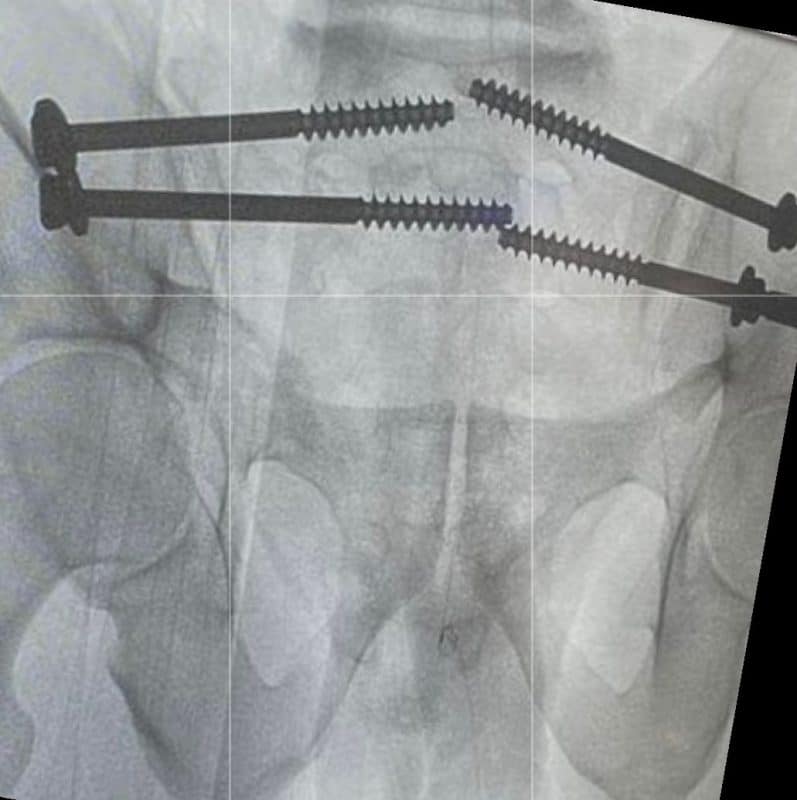

أوضحت “الصحة” أن فريقاً طبياً متخصصاً في قسم العظام في مستشفى الدرعية عضو تجمع الرياض الصحي الثالث تمكن من تثبيت كسر معقد في العظم العجزي في منطقة الحوض للمريض.

وقالت الوزارة إنه تم إرجاع، وتثبيت الخلع في المفصل العجزي الحرقفي لمريض في العقد السادس من العمر عن طريق وضع مسامير طبية باستخدام الأشعة التداخلية.

وأشارت “الصحة” إلى أنه الطريقة المثلى لعلاج مثل هذه الكسور، هي تثبيت الكسر بالطريقة المغلقة لتسهيل تأهيل المريض ومساعدته على التحرك بشكل أسرع، موضحة أن الإجراء يتم عن طريق فتحة في الجلد من 2 إلى 3 سم تحت التخدير العام.